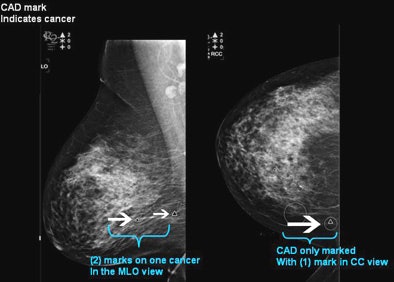

![]() |

| Left MLO view and the left CC view of a 52-year-old screening patient. CAD didn't mark the cancer on either view; density can be seen in the left superiolateral aspect. Biopsy revealed invasive carcinoma. |

At surgery, 10 cases were upgraded from in situ to invasive disease, for a total of 40/45 invasive cancers, she said. Eight of the 10 upgraded cancers were detected by CAD, she noted, including eight seen in both MLO and CC views, one found in the CC view only, and one tumor not seen on either projection or CAD.